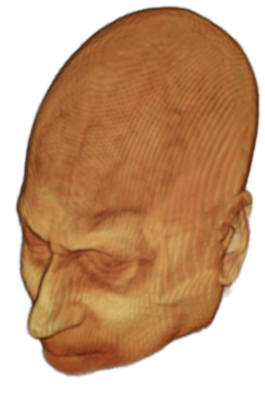

The digitalization of heath records has increased the risk of –and impact of– large scale data leaks. Although data compliance standards have been enacted to protect health records (HIPAA and GDPR), privacy of medical data is a growing concern. Three-dimensional scans such as magnetic resonance images (MRI) and computed tomography (CT), for example, contain an intrinsic privacy risk [Lotan et al.(2020)Lotan, Tschider, Sodickson, Caplan, Bruno, Zhang, and Lui]. Detailed renderings of the head can be crafted from 3D scans using techniques such as volumetric raycasting, as in Figure 1. This vulnerability can expose the patient’s identity if the renderings are matched to a face database [Mazura et al.(2012)Mazura, Juluru, Chen, Morgan, John, and Siegel, Lotan et al.(2020)Lotan, Tschider, Sodickson, Caplan, Bruno, Zhang, and Lui].

![]() |

Therefore, in this work, we define a new class of de-identification techniques that remodels the privacy-sensitive regions without altering the content of medically relevant data (see Figure 1). Under such a remodeling approach, the face, eyes, oral and nasal cavities, etc. should exhibit realistic appearance and structure of appropriate size, but should otherwise be independent of the original data. To solve this task, we propose a novel model called Convex Privacy GAN, or CP-GAN, that conditions on a convex hull of the skull extracted from the scan to be de-identified. The generator learns to synthesize volumes that preserve medically-sensitive regions such as the brain, while non-invertibly remodeling privacy-sensitive characteristics from the original scan.